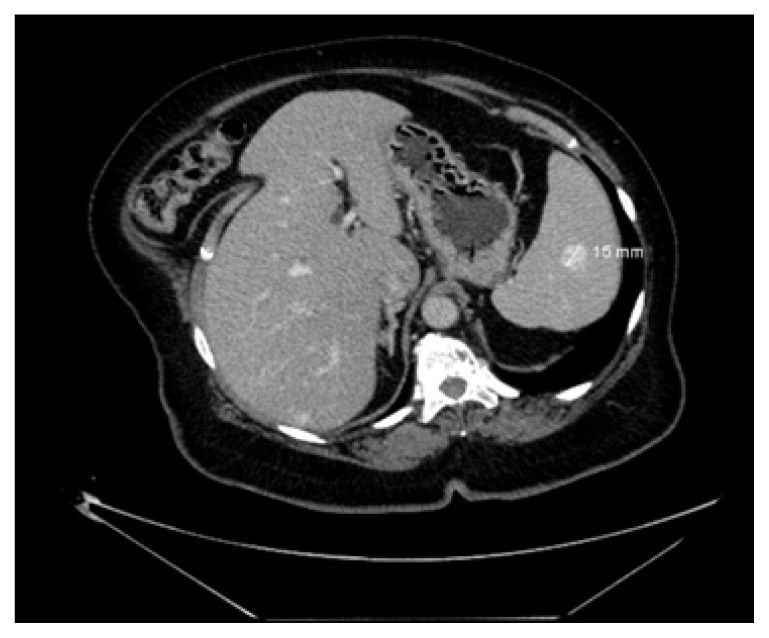

Recurrent Breast Angiosarcoma.

复发性乳腺血管肉瘤